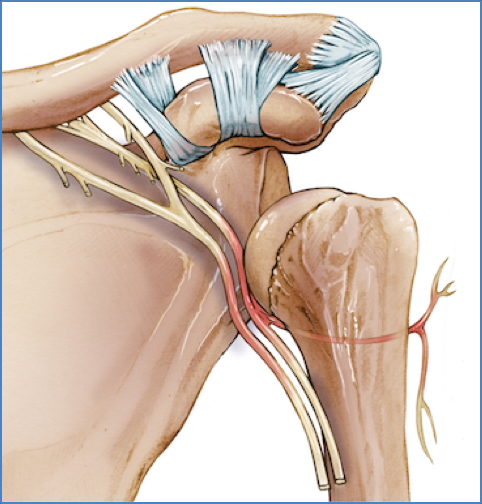

Dislocations and Nerve Injury Risks

- Shoulder Dislocation (Glenohumeral):

- Axillary nerve

- Musculocutaneous nerve

- Radial nerve

3. Hellerhoff, CC BY-SA 3.0 <https://creativecommons.org/licenses/by-sa/3.0>, via Wikimedia Commons

| Axillary | Shoulder dislocation | Loss of shoulder abduction (deltoid) | Skin over deltoid region |

| Musculocutaneous | Axilla | Weak elbow flexion | Lateral forearm |

| Radial (Axilla) | Axilla | Wrist drop; ↓ elbow extension | Posterior arm, forearm, hand dorsum |